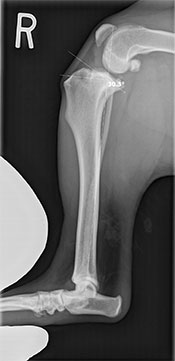

A thorough physical examination showed signs of positive cranial drawer and tibial thrust (unnatural movement) in the right knee. He was sedated and radiographs were taken, which showed arthritic changes in both his knees.

Dr. Edinger diagnosed him with bilateral cranial cruciate ligament (CCL) tears; completely torn on the right, and partially torn on the left. Due to Fen’s active lifestyle and the arthritis that was already present in both knees, Fen’s people elected to pursue bilateral Tibial Plateau Leveling Osteotomies (TPLO’s) to correct the instability in both of his knees.